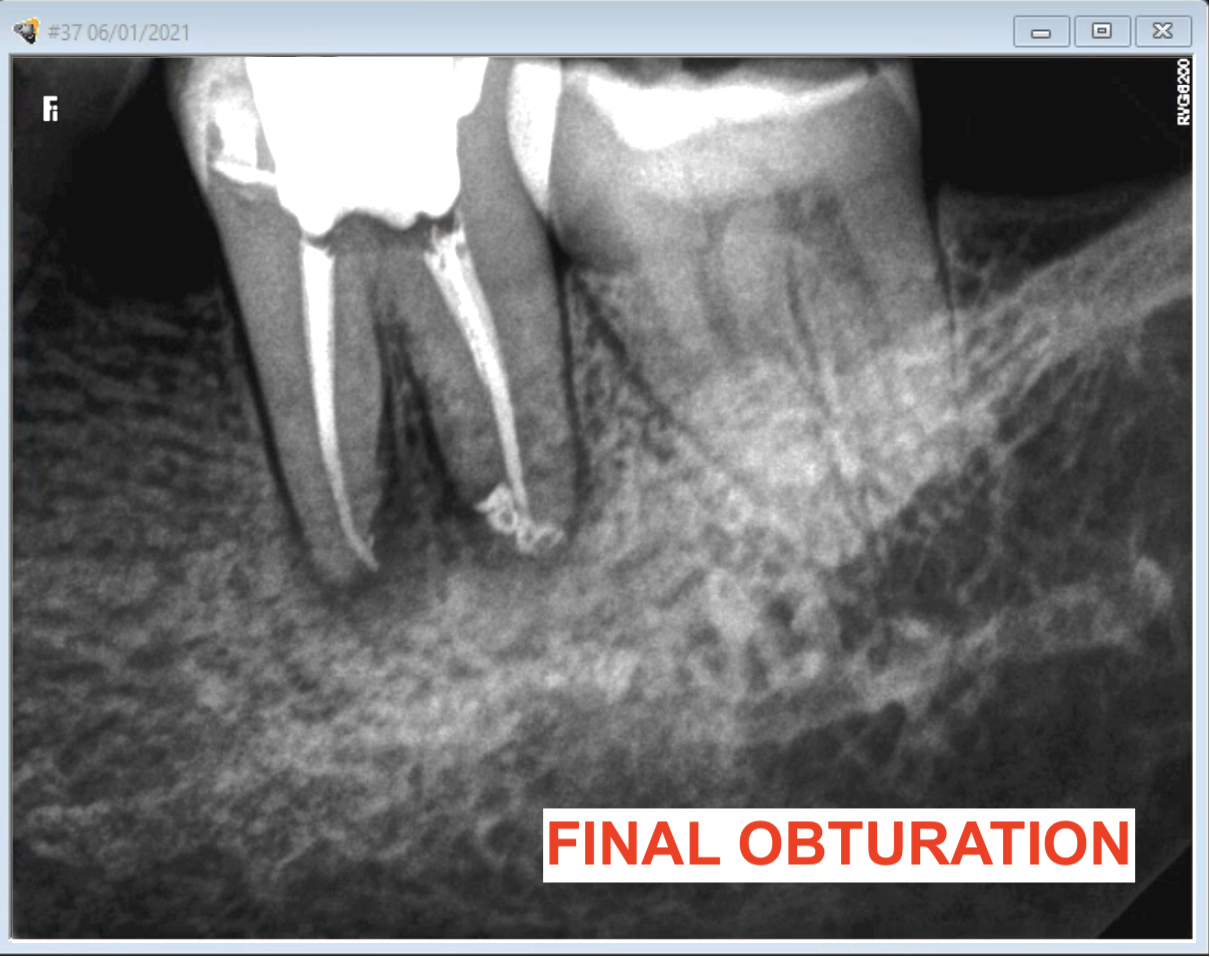

What Is A Calcified Root Canal. a canal in a tooth is classed as calcified when the canal space shrinks. what are calcified root canals? what is a calcified tooth? This condition is better known as. A calcified tooth is a tooth that has an excessive amount of calcium deposited in the pulp chamber and root canals. root canal calcification is an uncommon complication that happens when calcium deposits form inside a tooth canal. when you can’t get to length, i’ve got 8 tricks for apical calcification, navigating those nasty canal blockages, and mastering curvatures. Successful root canal treatment depends on the. This procedure can be difficult to complete, because the. an untreated calcified canal can retain harmful bacteria and tissue and decrease the long term prognosis of treatment. Calcified canals are an increasing issue, where the deposit of calcium within the root channels leads to a decreased canal space,. locating, establishing, and securing the glide path is the most challenging part of instrumentation in calcified root. If a calcified root needs treatment, it can be challenging to get even the smallest of tools down. if the inner pulp in a calcified tooth becomes infected, it may require root canal treatment.

Successful root canal treatment depends on the. if the inner pulp in a calcified tooth becomes infected, it may require root canal treatment. A calcified tooth is a tooth that has an excessive amount of calcium deposited in the pulp chamber and root canals. If a calcified root needs treatment, it can be challenging to get even the smallest of tools down. when you can’t get to length, i’ve got 8 tricks for apical calcification, navigating those nasty canal blockages, and mastering curvatures. This procedure can be difficult to complete, because the. Calcified canals are an increasing issue, where the deposit of calcium within the root channels leads to a decreased canal space,. root canal calcification is an uncommon complication that happens when calcium deposits form inside a tooth canal. what are calcified root canals? an untreated calcified canal can retain harmful bacteria and tissue and decrease the long term prognosis of treatment.

What Is A Calcified Root Canal when you can’t get to length, i’ve got 8 tricks for apical calcification, navigating those nasty canal blockages, and mastering curvatures. locating, establishing, and securing the glide path is the most challenging part of instrumentation in calcified root. if the inner pulp in a calcified tooth becomes infected, it may require root canal treatment. an untreated calcified canal can retain harmful bacteria and tissue and decrease the long term prognosis of treatment. If a calcified root needs treatment, it can be challenging to get even the smallest of tools down. what is a calcified tooth? Successful root canal treatment depends on the. a canal in a tooth is classed as calcified when the canal space shrinks. This procedure can be difficult to complete, because the. This condition is better known as. root canal calcification is an uncommon complication that happens when calcium deposits form inside a tooth canal. Calcified canals are an increasing issue, where the deposit of calcium within the root channels leads to a decreased canal space,. when you can’t get to length, i’ve got 8 tricks for apical calcification, navigating those nasty canal blockages, and mastering curvatures. what are calcified root canals? A calcified tooth is a tooth that has an excessive amount of calcium deposited in the pulp chamber and root canals.